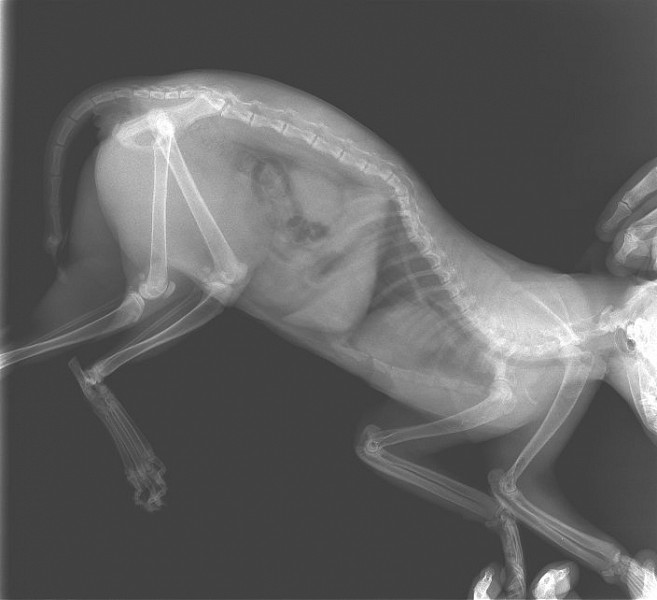

Рентген Задней Лапы Кошки: Нормы и Диагностика